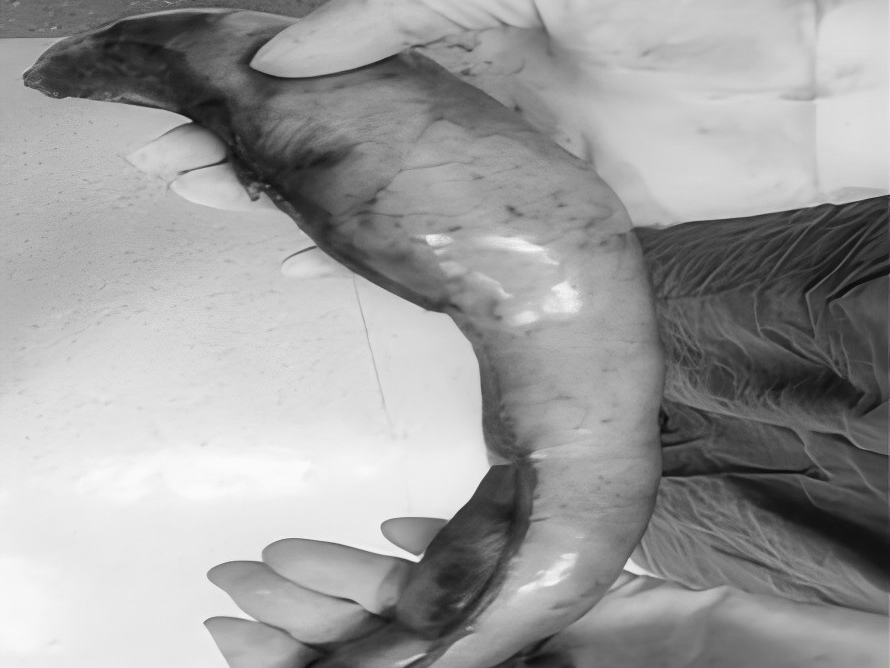

为深入践行人才强院核心战略,加速打造高水平医疗专家团队,引领学科跨越式发展,7月15日,贵州航天医院成功签约(柔性引进)知名肛肠外科专家高大勇教授,并举行“高大勇教授名医工作室”授牌仪式。贵州航天医院党委书记杨军,院长廖江荣,副院长彭亮、马庆庆、蒋婷出席仪式,普外科全体医护人员参加。 仪式上,杨军为高教授颁发了聘书,双方共同签署了合作协议,高教授授予普外科“名医工作室”函牌。 聘书颁发 柔性人才引进协议签约 名医工作室授牌 仪式后,高大勇教授前往科室开展早交班、教学查房等工作,针对疑难病例给予专业的治疗建议和科学指导。 此次柔性引进高大勇教授并设立名医工作室,将进一步促进贵州航天医院普外科在学科建设、技术创新、人才培养、科研教学等方面能力的提升,推动我院肛肠疾病诊疗能力实现跨越式发展,为广大患者带来优质医疗服务。 贵州航天医院普外科专家团队 高大勇 普外科(肛肠外科)学科带头人、名誉主任,主任医师、教授 临床擅长:对中西医结合诊治肛肠学科各种常见病、多发病及疑难杂症等具有丰富的临床经验。 原遵义市第一人民医院(遵义医科大学第三附属医院)、遵义市中医院肛肠科主任。中华中医药学会肛肠分会常委,全国中医肛肠学科名专家,中国健康促进与教育协会肛肠分会常委,中国康复医学会肛肠疾病康复专业委员会常委,中国民间中医医药研究开发协会肛肠分会副秘书长,中国医师协会中西医结合肛肠医师专业委员会常委,国家二级心理咨询师,贵州省第一批中医名医工作指导老师,遵义市名中医,遵义市肛肠学会会长,遵义市肛肠质控中心名誉主任,遵义市中西医结合学会名誉会长,遵义市健康科普专家,原贵州省中西医结合学会肛肠分会副主任委员、贵州省中医肛肠质控中心副主任、遵义市医学会医疗鉴定委员会专家、遵义市卫生系列高评委。发表论文30余篇,主编和参编医学著作5本,主持省级科研课题2项、市级科研课题2项、院级科研课题1项。 梁 跃 中共党员,普外科党支部书记、主任,主任医师 临床擅长:对普外科各类肿瘤手术具有丰富的临床经验。 毕业于遵义医学院,遵义市医学会小儿外科学分会常务委员,遵义市肛肠协会理事,遵义市医学会核医学分会(第二届)委员会委员;荣获第三期“黔医人才计划”优秀学员称号;主持市级课题1项,完成省级课题1项,在国内各类刊物上发表论文10余篇。 钱科洪 民盟盟员,普外科副主任医师 临床擅长:从事普外科临床工作30余年,对各类普外科疾病的诊治,乳腺、甲状腺、胃十二指肠、结直肠等疾病及疑难杂症诊治具有丰富的临床经验。 毕业于遵义医学院临床医疗系,2009年前往中山大学附属第一医院微创外科进修学习,在国内各专业期刊发表论文数篇。 贵州航天医院普外科简介 基本情况 贵州航天医院普外科成立于1968年,前身属于航天部O61基地3417医院外一科,1998年3417医院、3427医院合并后更名为普外科,下设胃肠外科、肛肠外科2个亚专业科室,拥有在全市较为先进的专科设备和技术,是中国疝病专科联盟单位,贵州医科大学附属医院胃肠外科专科联盟单位。开放床位40张,配备医护人员21人。 专科特色 普外科致力于胃肠及肛肠疾病的外科临床诊治及科研,以腹腔镜微创外科技术为本,形成以快速康复治疗胃肿瘤、结直肠肿瘤、小肠肿瘤、直肠脱垂、肥胖病、急腹症、各类疝、痔、瘘等专科特色,同时注重胃肠疾病尤其是结直肠恶性肿瘤的基础研究和临床转化研究,总体诊断和治疗水平在区域同级医院居于领先水平。 开展手术:腹腔镜下胃癌根治术,腹腔镜下袖状胃切除术,腹腔镜下胃肠道间质瘤切除术,腹腔镜下结、直肠癌根治术,胃癌、结直肠癌的精准治疗,腹腔镜下小儿疝气、成人疝修补术,腹腔镜下阑尾手术,内痔的硬化注射治疗及痔疮的微创治疗:ATH、PPH、TST,直肠脱垂的各种手术治疗,难治性伤口VSD技术,鼻胃肠管、肠梗阻导管置入术,肛肠术后间歇性导尿技术,并引进了中医适宜技术,也为各种化疗患者提供输液港安装,提高患者就医体验。 腹腔镜下腹股沟 疝无张力 修补术 腹股沟疝里金 斯坦(Lichten stein)手术 PPH微创术治疗环状混合痔 黏连性或炎性肠梗阻-肠梗阻导管 腹腔镜袖状胃切除 腹腔镜阑尾切除术 腹腔镜阑尾肿瘤切除术 腹腔镜下结肠癌根治术 诊疗范围 胃肿瘤、结直肠肿瘤、小肠肿瘤、肥胖症、各类急腹症、腹部外伤、腹壁疝、便秘、直肠脱垂、痔疮、肛瘘、肛裂等胃肠、肛肠外科疾病。 END